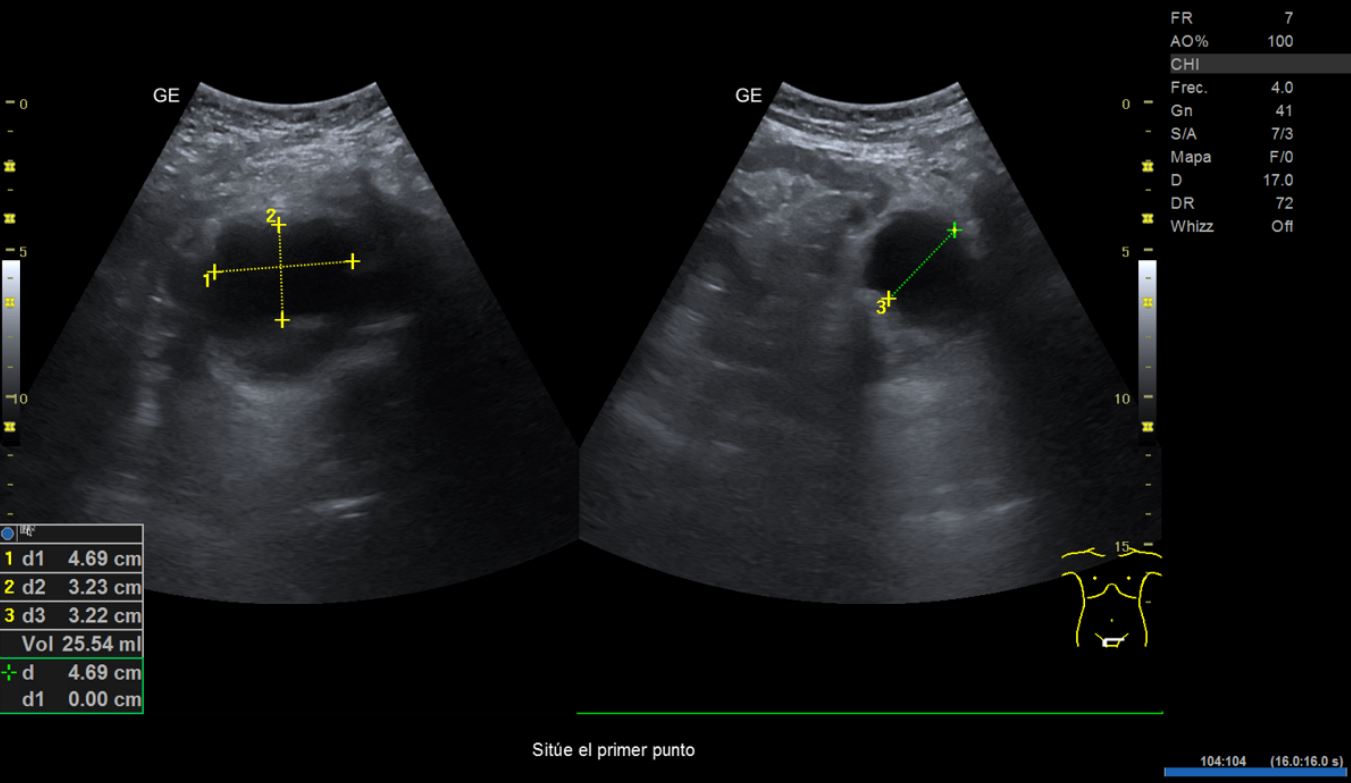

• Ecografía clínica renovesical: riñones con diámetro dentro de la normalidad. Relación cortico-medular normal. Pedículo renal Doppler normal. No se observan litiasis. Vejiga repleta, paredes finas, se observa imagen hipoecogénica en pared posterior lateral derecha que no capta señal Doppler, de unos 2,21 cm de diámetro aproximadamente. Volumen premiccional 290,86 ml, volumen posmiccional 25,54 ml.

En primer lugar se derivó a ginecología por sospecha de sangrado de origen ginecológico donde visualizan ecográficamente un grosor endometrial de 5-6 mm y realizan una biopsia endometrial con resultado de escasos fragmentos superficiales de endometrio atrófico. Tras descartar origen ginecológico y ante la persistencia del sangrado, se orienta como hematuria monosintomática y se realiza una ecografía en el centro de Atención Primaria donde se visualiza imagen hipoecogénica dependiente de la pared vesical.